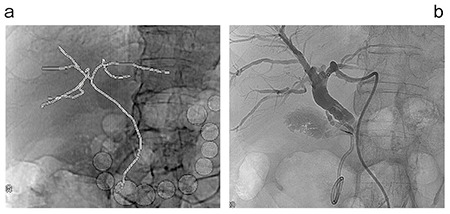

図2は、術後に直腸断端に仮性動脈瘤が認められた症例で、左の内腸骨動脈末梢の蛇行した血管の先に出血部分が認められた。手技を行うに当たって仮想透視画像を作成し、蛇行血管のカーブの形状を把握しやすいCアームのワーキングアングルを検討したところ、LAO27°が最適と思われた。実際にその角度での血管走行を把握して手技を行ったところ、スムーズにカテーテルを進めることができた。仮想透視画像は3Dデータであり、画像上で任意の角度に振ることができるため、どの角度で見れば最も手技を行いやすいかを術前に把握して実際の手技に臨むことができる。また、骨だけではなくドレーンやチューブ、ステープラーやパッキングされたガーゼなども透視と同様に表示されるため、それらを目安にして手技に生かすこともできるのがメリットである。

図2 術後直腸断端仮性動脈瘤症例

内腸骨動脈の末梢の出血に対して蛇行した血管走行が見やすいワーキングアングルを把握して手技ができる。